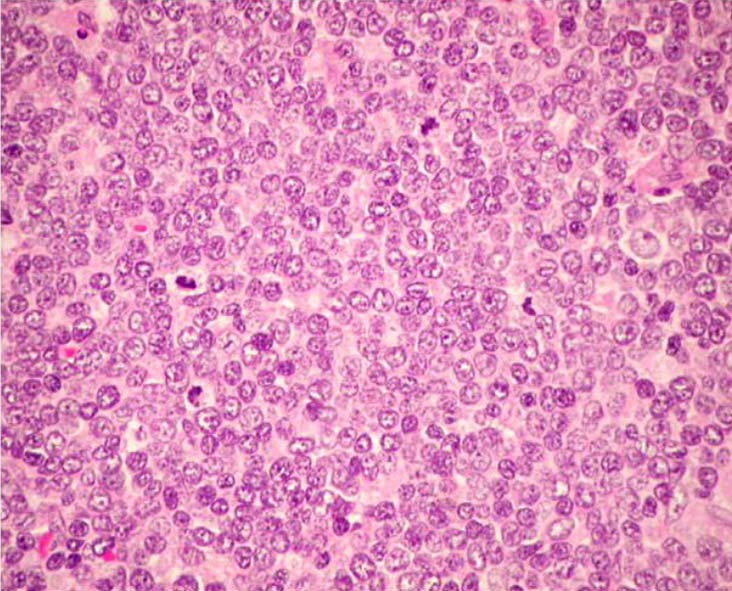

低倍率で見る増殖腫瘍細胞の単調さ, 均質さがきわだつことがMCLの診断に重要な所見である。均一な細胞の形態には, いろいろなヴァリエーションが見られる。

大きさの均一な小型ないし中型の細胞が増殖している。細胞質は乏しく, 不整で, でこぼこな(indented)核に中等度に粗いクロマチンが認められる。核小体は見えにくい。(核小体が明瞭なものはpleomorphic variantやMCL以外のリンパ腫を疑う。) 切れ込みのある核もしばしば出現する。小型円形核のリンパ球はT細胞で種々の程度に混在する。

リンパ芽球型リンパ腫細胞のような繊細な核クロマチンでN/C比が高い類円形腫瘍細胞から成る。核分裂が多い。

腫瘍細胞は脳回状にくびれた中ないし大型核をもつ。核小体も明瞭なものが出現する。核形態、細胞のサイズともに多形性に富む。HEではATLLなどのT細胞腫瘍やびまん性B細胞性リンパ腫の腫瘍細胞に似る。